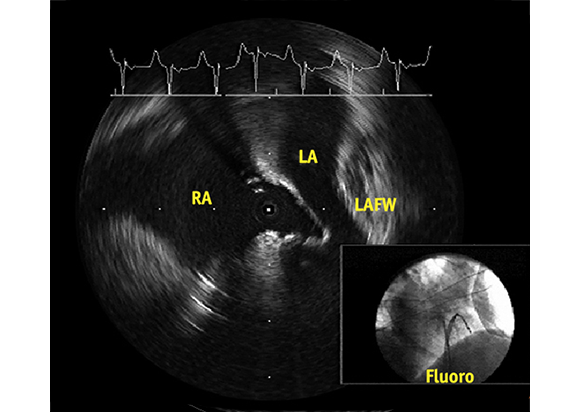

See What You Want to Avoid

Notice the patient’s reduced Left Atrium, the tenting of the septum and its relationship to the LAFW. The corresponding fluoroscopic image may suggest that puncture has already occurred. However, the ULTRA ICE PLUS image shows that this is not the case and guides the physician to redirect the needle in a puncture angle away from the LAFW.